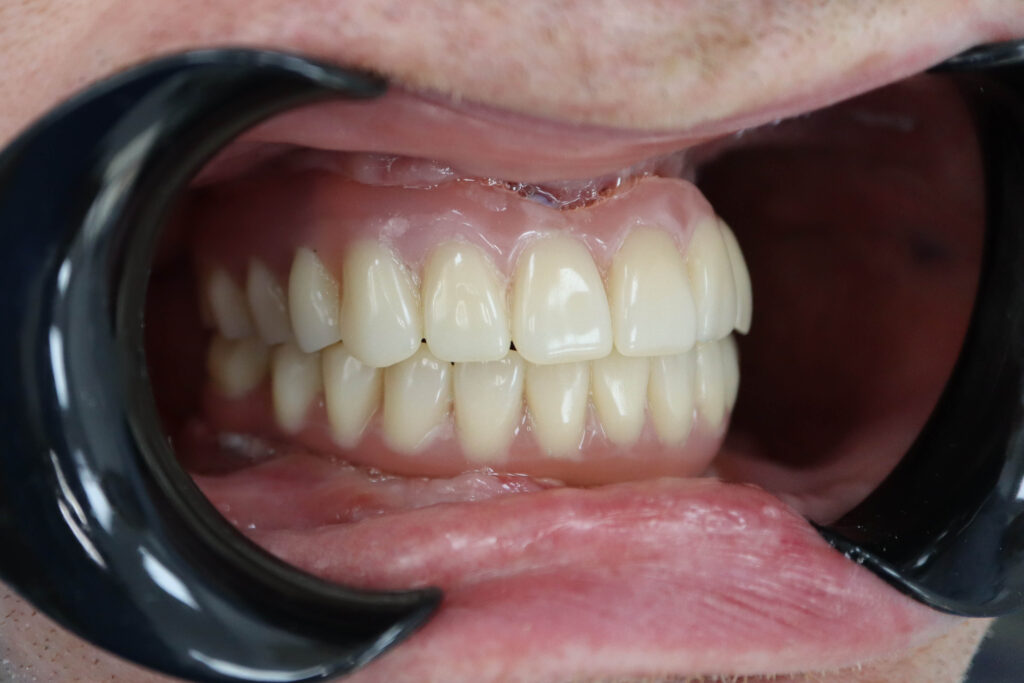

Результат

Результат имплантации

Спустя 7 дней на верхней и нижней челюстях зафиксированы металлоакриловые протезы из 12 зубов.